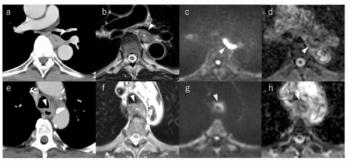

Through AI-powered assessment of coronary computed tomography angiography (CCTA) scans, the CaRi-Plaque software may provide improved clarity on the development of coronary plaques and luminal stenosis.

Offering the promise of improved insights into coronary plaques and luminal stenosis, the artificial intelligence (AI)-enabled CaRi-Plaque software has garnered 510(k) clearance from the Food and Drug Administration (FDA).

By ascertaining the extent and severity of coronary plaque and luminal stenosis, Caristo Diagnostics said the CaRi-Plaque software may facilitate earlier detection of coronary artery disease (CAD) in high-risk patients.